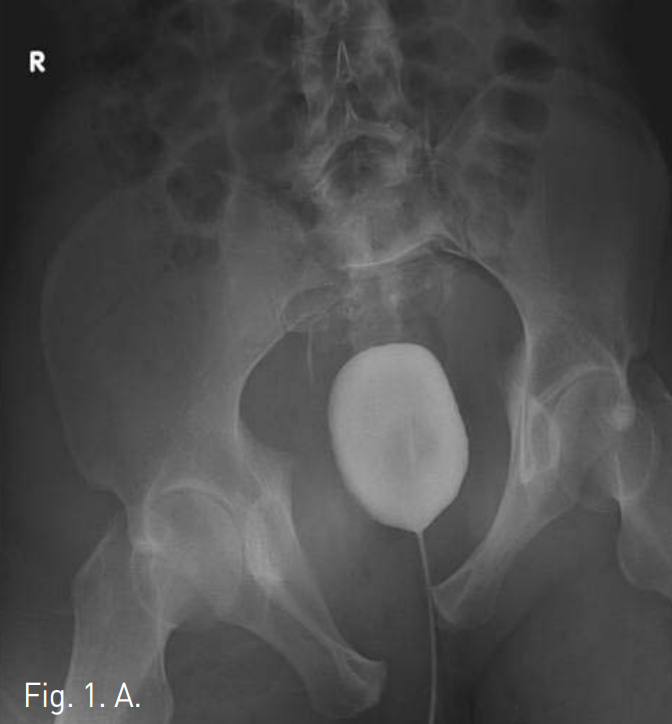

Emergency abdominal CT was performed to evaluate bleeding focus. Cystogram and abdominal CT revealed an extraperitoneal hematoma of the suprapubic area and marked widening of symphysis pubis(Fig 1). The CT findings were highly suggestive of inferior epigastric and obturator arterial injury. Enhanced study showed an extravasation within the mass indicative of arterial bleeding.

Fig 1.

A. Cystogram shows an external compression of the bladder, suggestive of perivesical hematoma, associated with diastatic fracture of the symphysis pubis.

B. Pelvic CT shows a hematoma with extravasation of contrast in pubic area (arrow), indicating active hemorrhage.